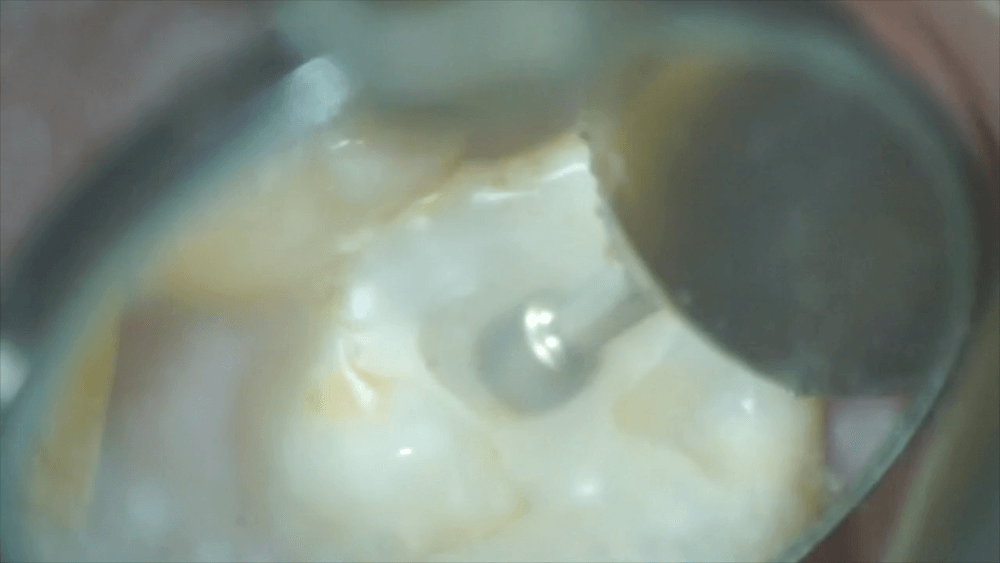

このつめ物をマイクロスコープを用いて除去します。

取り除くと、となりの歯の側面が見えました。黒くなっています。これは虫歯になりかかっている状態です。

この部分を触ると、虫歯の原因であるプラークがたくさん出てきました。